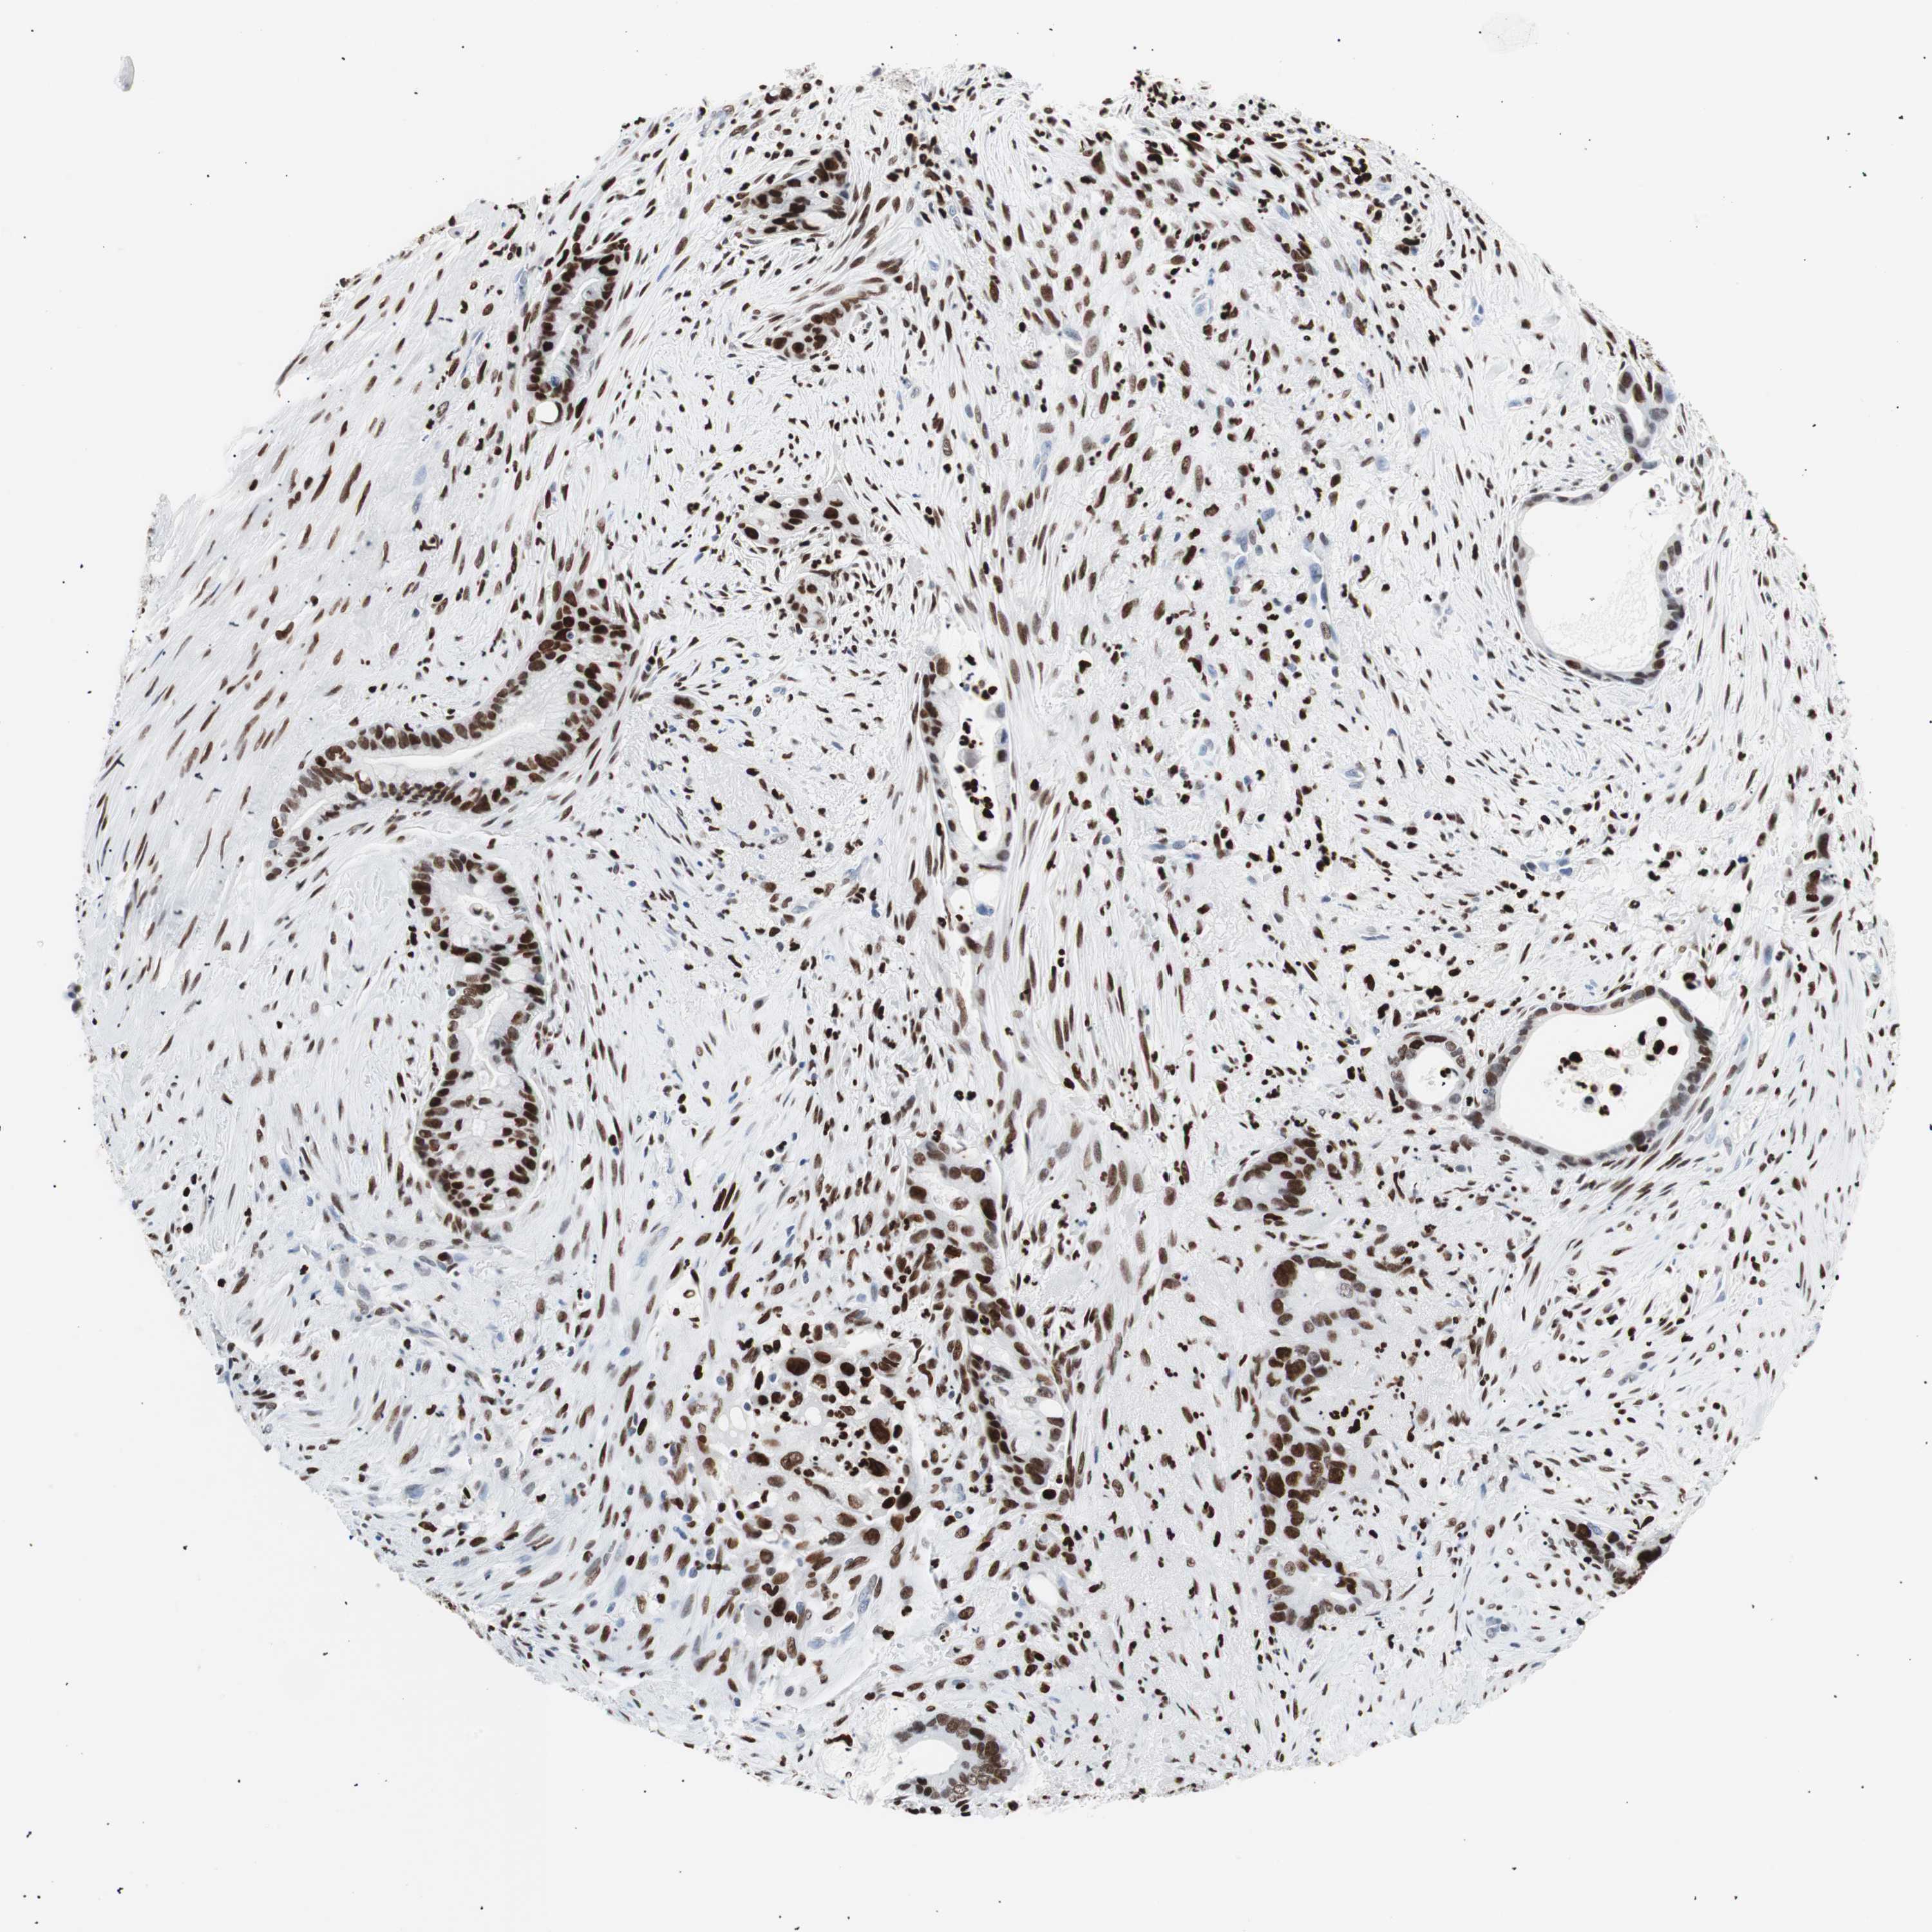

LIVER CANCER - Protein expressioni

A mouse-over function shows sample information and annotation data. Click on an image to view it in a full screen mode. Samples can be filtered based on level of antibody staining by selecting one or several of the following categories: high, medium, low and not detected. The assay and annotation is described here.

Note that samples used for immunohistochemistry by the Human Protein Atlas do not correspond to samples in the TCGA dataset.

Antibody stainingi

Antibody staining in the annotated cell types in the current human tissue is reported as not detected, low, medium, or high, based on conventional immunohistochemistry profiling in selected tissues. This score is based on the combination of the staining intensity and fraction of stained cells.

Each image is clickable and will lead to virtual microscopy that enables deeper exploration of all samples and also displays staining intensity scores, fraction scores and subcellular localization as well as patient and tissue information for each sample.

Antibody CAB004213

Staining

High

Medium

Low

Not detected

Intensity

Strong

Moderate

Weak

Negative

Quantity

>75%

75%-25%

<25%

None

Location

Nuclear

Cytoplasmic/membranous

Cytoplasmic/membranous,nuclear

Cholangiocarcinoma

Carcinoma, Hepatocellular, NOS